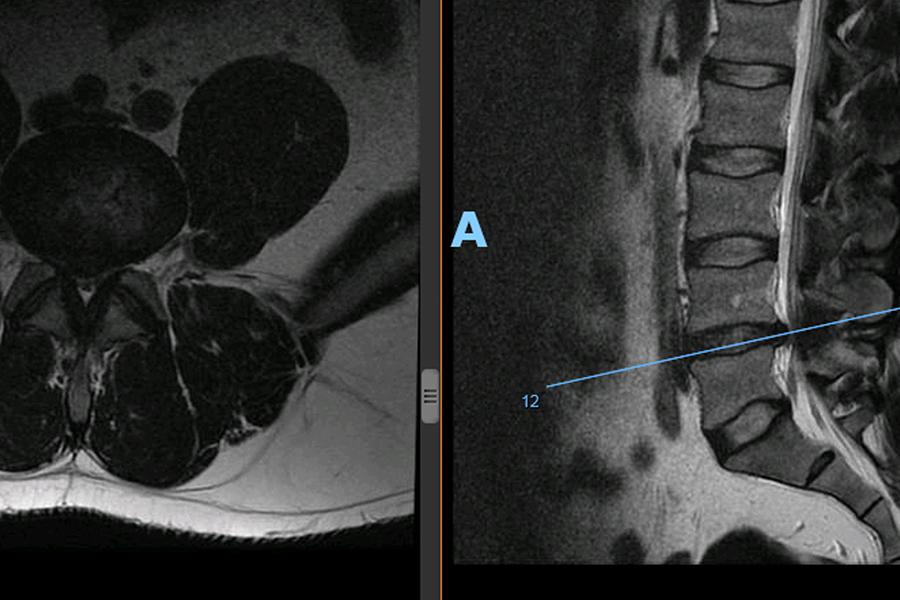

Caso clínico: endoscopia de columna multinivel L4L5 y L5S1

Los síntomas que presentaba el paciente eran dolores acentuados en las piernas, claudicación a la marcha y calambres y hormigueos en las piernas.

Durante la intervención quirúrgica, se abordarán los dos niveles mediante la técnica de endoscopia de columna.